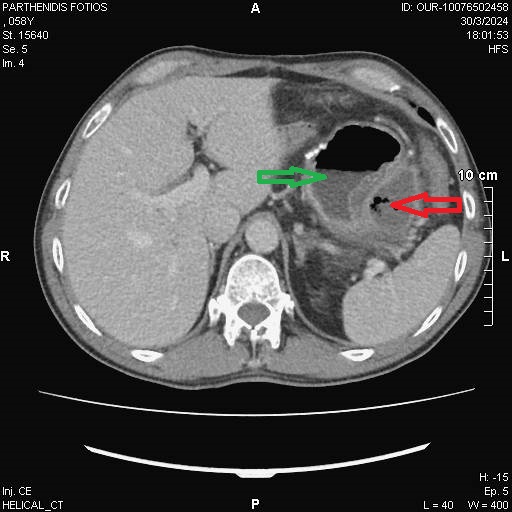

Πράσινο βέλος — Στόμαχος. Κόκκινο βέλος — Απόστημα (Ευγενική παραχώρηση Dr. V. Penopoulos).